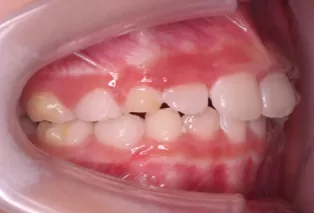

Intraoral photos